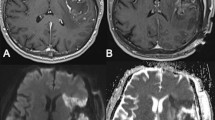

Case 1 (see Fig. 2a)

71-year old female (patient #1) with right temporal (inferior temporal gyrus) WHO grade II oligodendroglioma. IoMRI showed only a very slight band-shaped DWI restriction at the resection cavity. Because ioMRI showed no remaining tumor remnants, no further resection was performed after ioMRI. However, poMRI showed a clear enlargement of the infarcted tissue area, ultimately involving deeper parts of the parenchyma (sector-shaped infarct, relative infarct volume growth + 2.5 cm3). However, the patient did not exhibit any new neurological deficits postoperatively.

Case 2 (see Fig. 2b)

38-year old female (patient #4) with WHO grade II astrocytoma located in the cingulate gyrus. IoMRI showed no tumor residuals and no obvious signs of DWI restrictions. Discrete DWI hypointensity correlated to blood degradation products in SWI images and was therefore not accounted as an infarct. No additional resection or extensive hemostasis were performed after ioMRI. However, poMRI clearly showed a new sector-shaped infarct of about 1.93 cm3. Postoperatively, the patient presented with a new arm paresis and hypesthesia, which revolved completely over time.